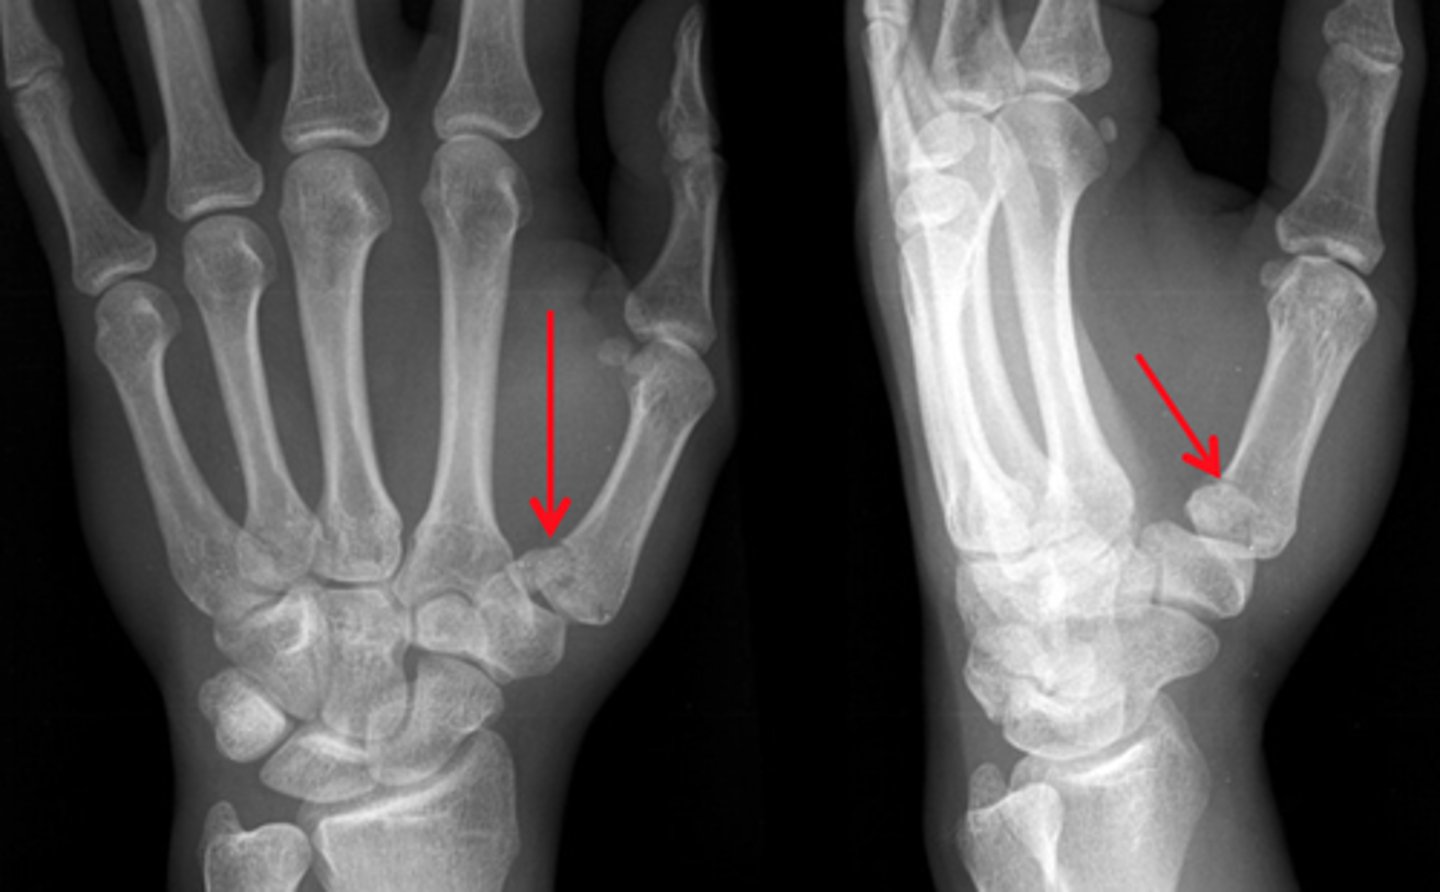

Fracture of distal fifth metacarpal

Boxer's fx